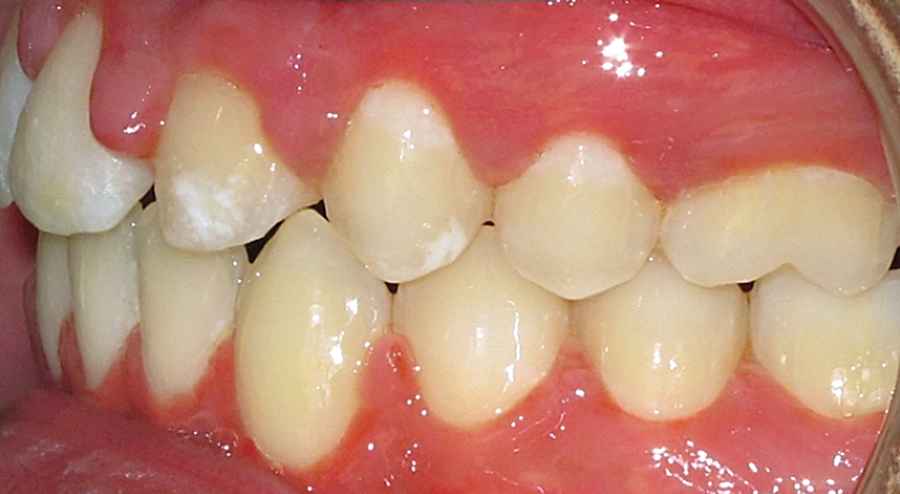

Figure 4F.

INTRODUCTIONTreatment planning for missing maxillary lateral incisors is a common clinical predicament encountered by orthodontists, particularly at Holland Bloorview Kids Rehabilitation Hospital where congenital absence of maxillary lateral incisors is a common feature of many of our patients afflicted by syndromal or non-syndromaloligodontia. Three main treatment options exist including: canine substitution; a tooth supported restoration; … Read more